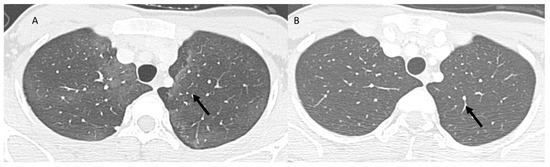

| Pulmonary lymphangitis carcinomatosa | Diffuse (related to the phase of disease) | Irregularly interlobular septal thickening; smooth (early stage) or nodular thickening (late development); ground-glass opacities; pleural effusions. | Tumor spread through lymphatic vessels |